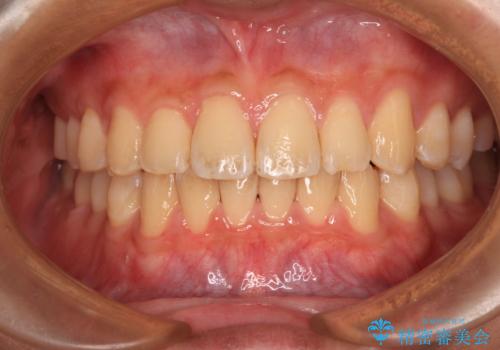

- 口元の突出感を気にして来院された患者様です。

左右ともに上顎奥歯が外を向き、下顎奥歯が内側に倒れているシザーズバイトであったため、補助装置により改善することとしました。

上下の咬み合わせは、下顎に対して上顎が相対的に前方にあったため、奥歯のシザーズバイト改善後に上顎左右第一小臼歯2本を抜歯し、上顎前突を改善していくこととしました。

左側の咬み合わせと上下正中の位置をコントロールするために時間がかかりましたが、事前に思い描いた通りの歯列に整い、患者様には大変満足していただきました。